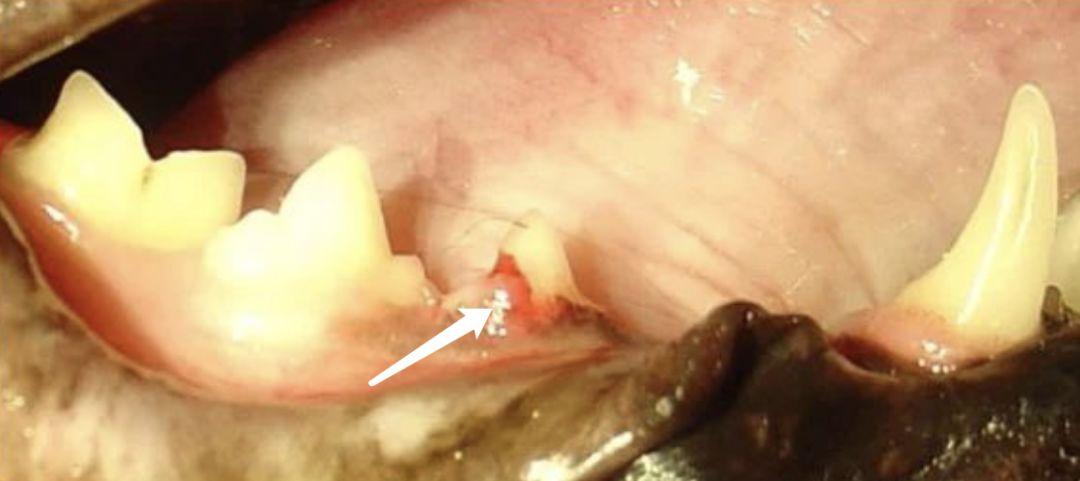

下图这口牙,第三课前臼齿,有牙吸收的问题,已经出现牙龈增生(见箭头)。

被牙吸收侵蚀的牙齿通常会出现在牙龈的边缘,表面被侵蚀或再吸收。但是这些病变组织往往会被牙结石或者牙龈增生组织(多长出来的牙龈组织)所覆盖,因此你可能看不到。

通常先是牙骨质和牙本质先行被侵蚀,而后向牙髓腔渗透。紧接着牙吸收会继续随着牙本质小管进入牙冠。牙釉质也会被侵蚀,甚至导致牙齿破裂。牙骨质和牙本质最后会被骨样组织取代。

有时候你可以清晰的观察到牙吸收,但是更多时候需要拍摄 X 光才能看到。因此一般肉眼就能看到的时候,已经比较严重了。